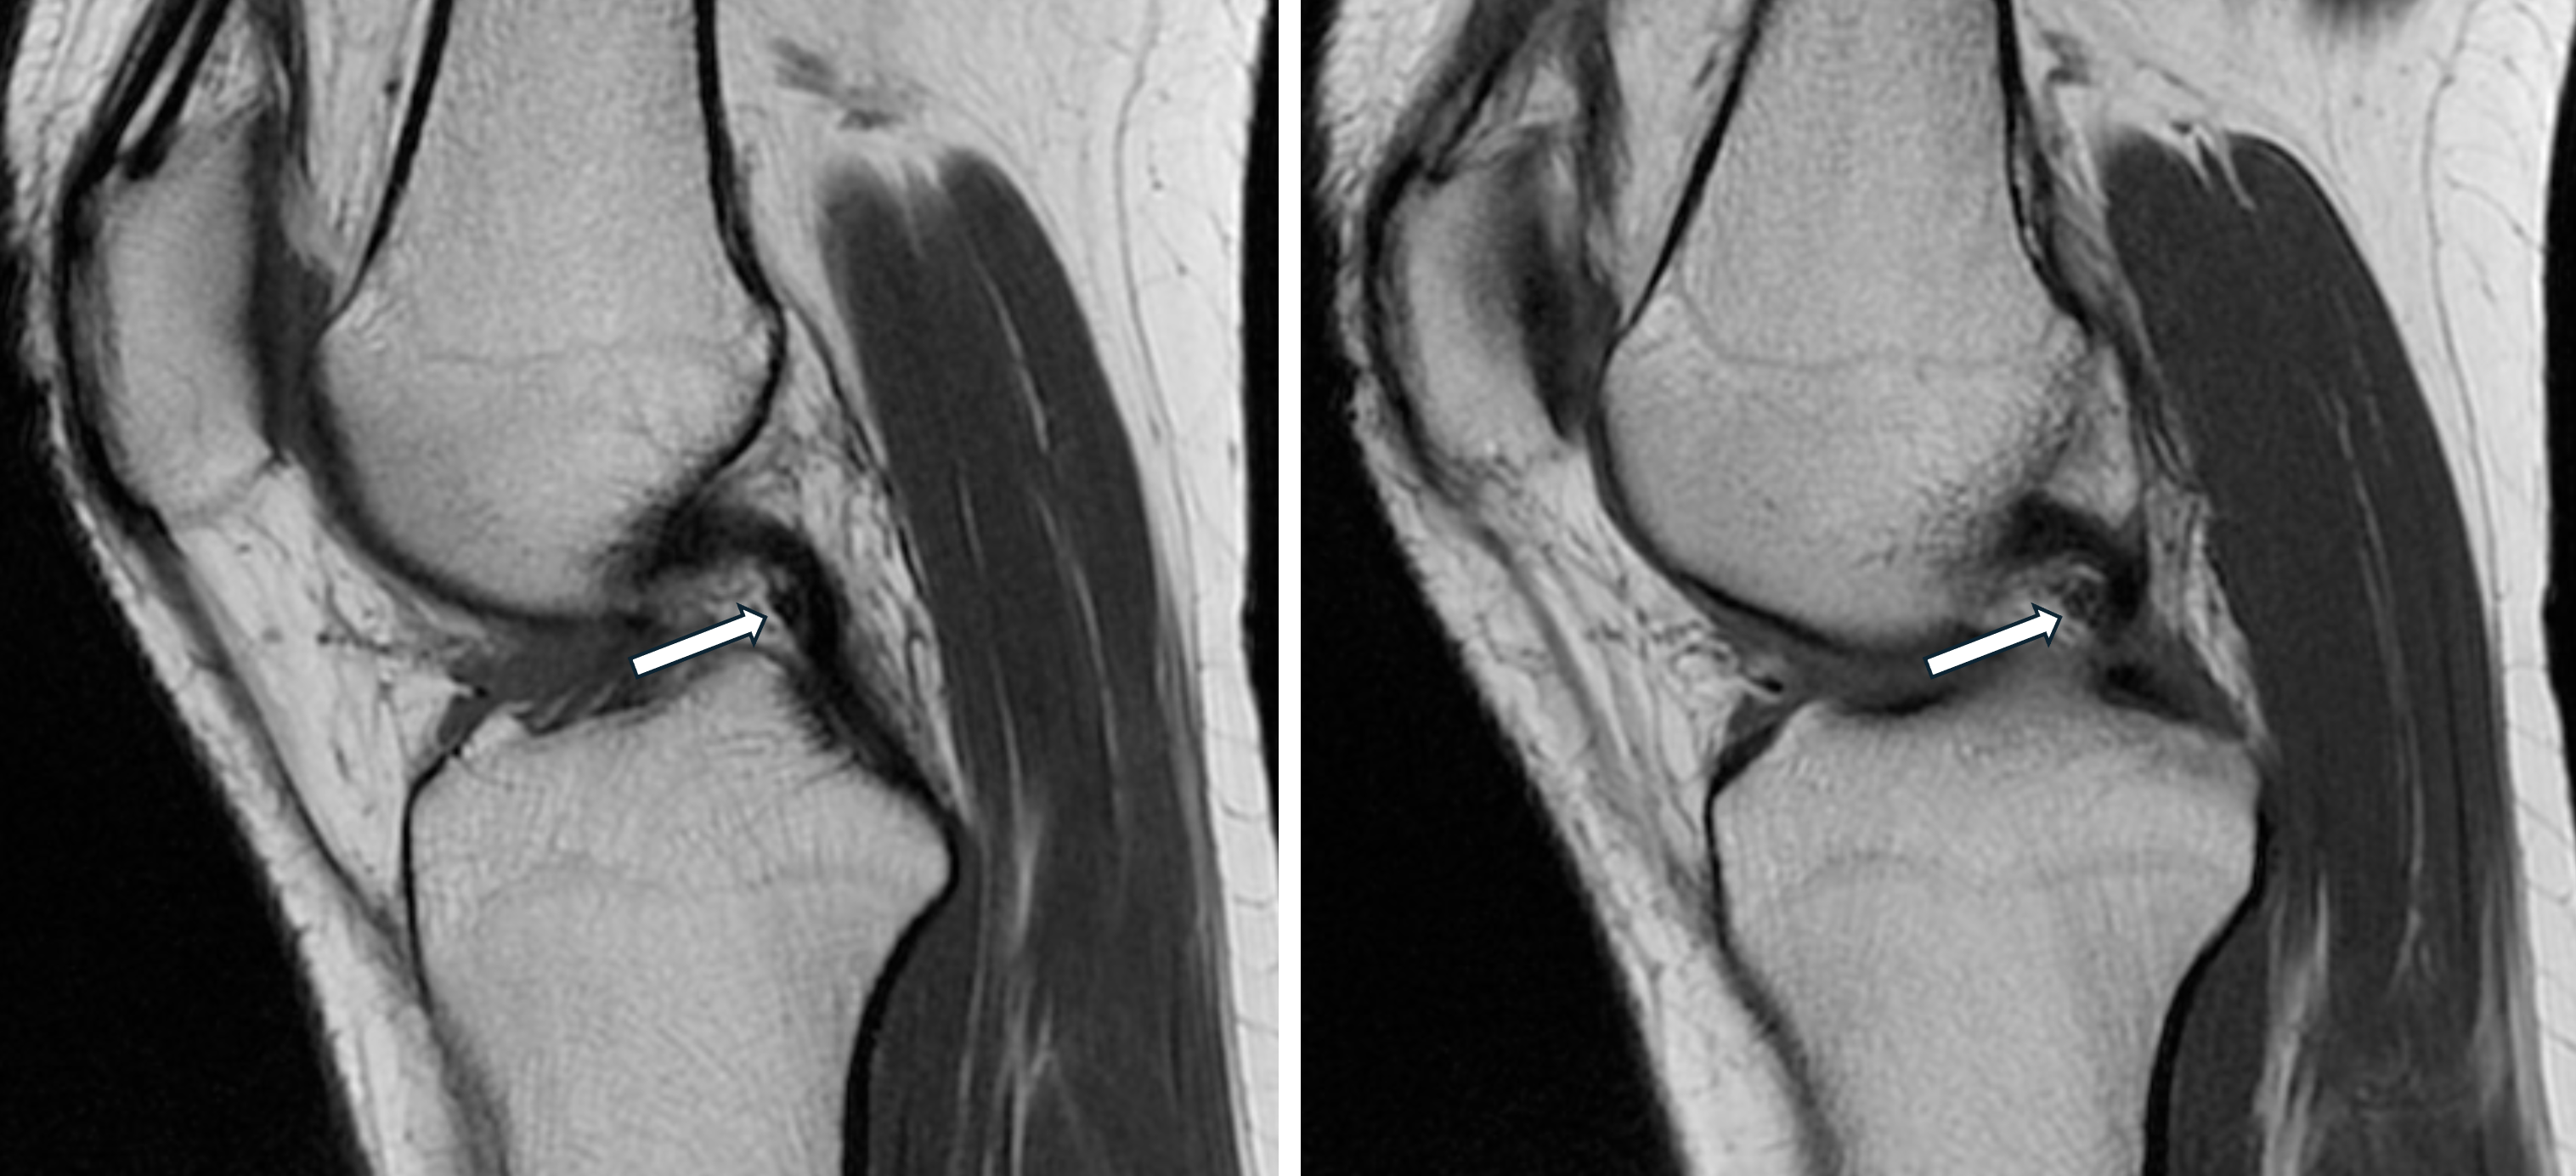

Welche Normvariante ist auf den zwei konsekutiven sagittalen T1-gewichteten Schichten eines Knie-MRTs (Pfeile) dargestellt?